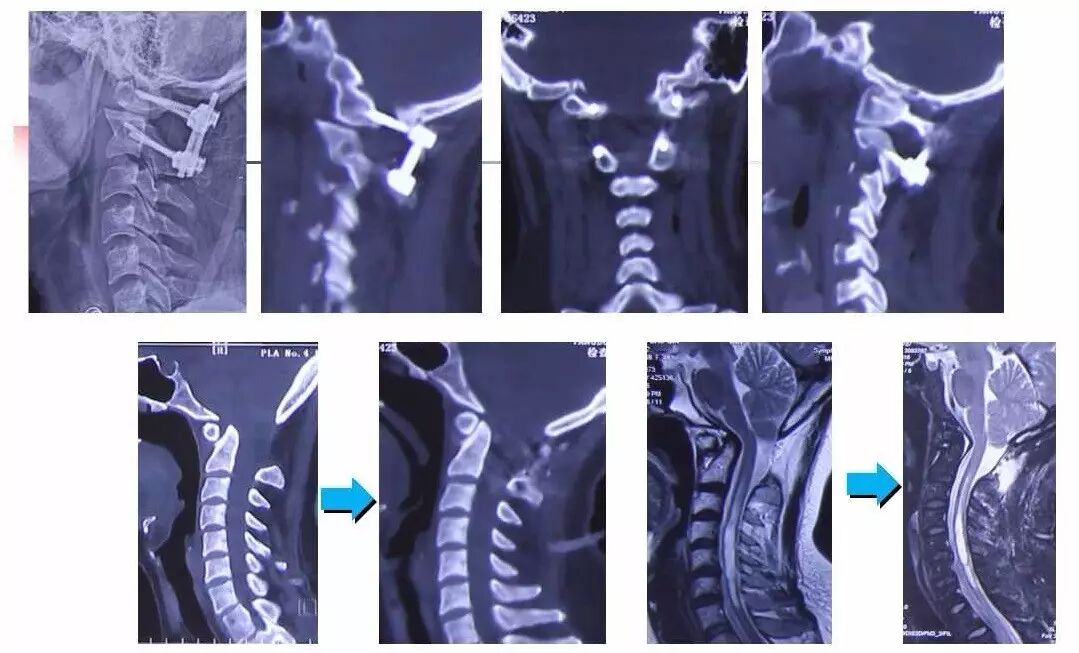

在脊柱神经外科、显微神经外科和颅底肿瘤外科前沿研究和临床诊治领域有着扎实的基础,为全国首批获得脊柱神经外科医师培训认证的神经外科医生。擅长颈椎病、椎管肿瘤及各种脊柱疑难疾病的诊治、脑肿瘤微创手术,尤其擅长颈椎退行性疾病的手术,率先在国内开展了颅底凹陷后路复位、颈前路减压融合等高难度手术,多年来收治了来自全国各地的大量患者,疗效达到国内领先水平。